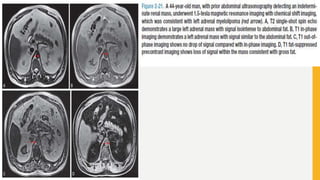

Adrenal Adenoma

• Adrenal adenomas are characterized by assessing the lipid content within cells. CSI

uses the difference in the behavior of water protons (H2O) versus fat protons (-CH2-).

The oxygen atom in water pulls on the electron cloud surrounding the hydrogen atom,

whereas the carbon atom in fat is less electronegative and has a decreased effect on

the hydrogen electron cloud. This difference in the magnetic field (shielding) for these

two types of protons is the precessional frequencies or the chemical shift.

• CSI obtains images “in-phase” (IP) and “out-of- phase” (OP) with regard to the water

and fat protons. The signals detected for a given voxel can be additive or cancelled

out. The IP imaging refers to the contribution of both fat and water, or additive to the

signal at a given voxel. This occurs when the echo time (TE) is set to align the fat and

water protons.

• In the OP imaging, the TE is set to cancel the signals obtained, thus the

subtraction of the protons results in a decrease, or cancelling, in signal at that

given voxel and produces a lower SI if both fat and water are present.

• The next step is to compare the two data sets (IP and OP) obtained to determine if

there is a loss of signal (decrease) on the OP images, which is indicative of

intracytoplasmic fat. If there is no change between the two data sets, then there is a

lower probability that fat is present within the mass. This was initially determined on a

qualitative basis by visually comparing signal intensities between the two sequences.

• The loss of signal on CSI is 92% sensitive and has a limited specificity of 17% for

adrenal adenoma.

• In some clinical situations, lipid poor adenomas (10% to 30% incidence) can result in

an indeterminate study .

• The typical washout of an adrenal cortical carcinoma is slow.

• Therefore an enhanced CT with washout may be a better study to differentiate lipid-

poor adrenal adenomas from other adrenal masses .